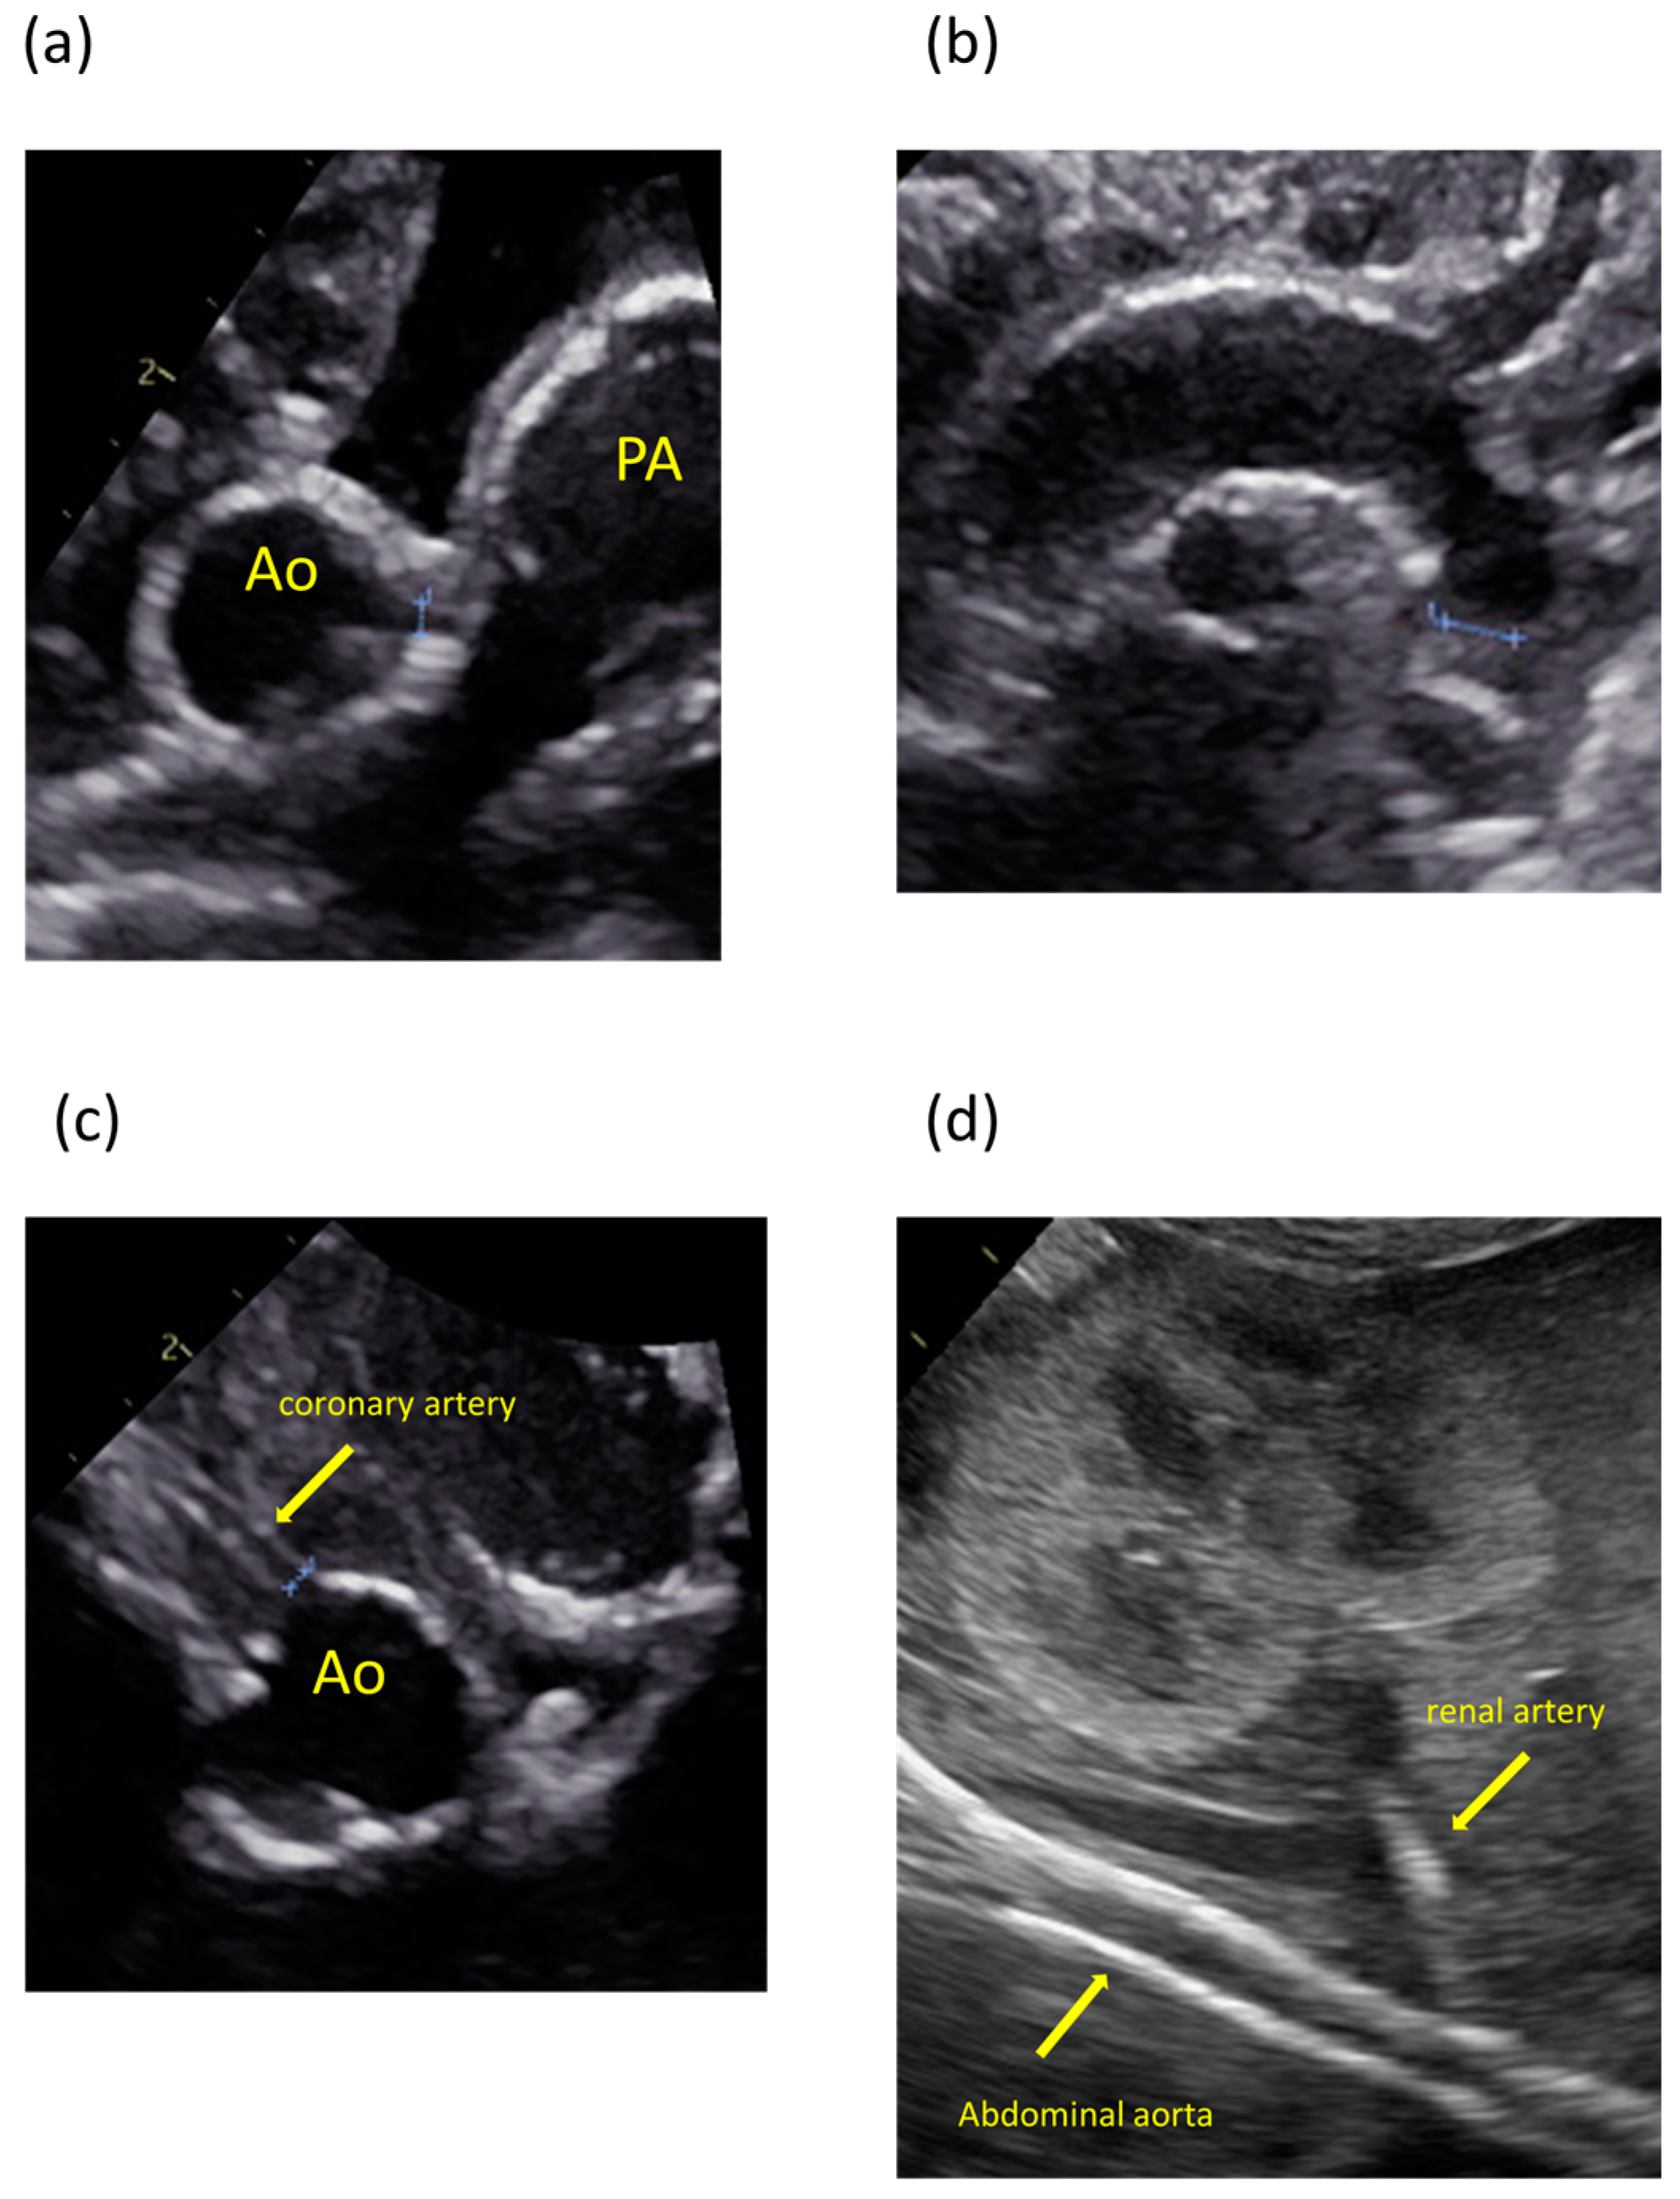

2. Case Presentation